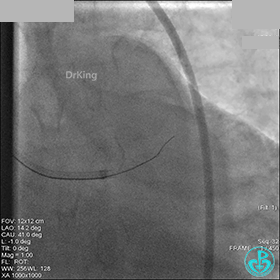

冠脉造影

入院次日冠脉造影显示粗大左主干末端中度狭窄,前降支开口严重狭窄,回旋支与前降支角度大,弥漫性长病变,严重狭窄,粗大右冠脉近中段弥漫性中重度狭窄。由于病变复杂,造影结束后先下台,择期再行介入治疗。